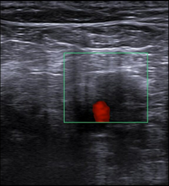

En ecografía clínica realizada por dolor de rodilla derecha se aprecia en región posterior vena poplítea que no comprime. En modo Doppler: defecto de repleccion del vaso por probable trombo intraluminal.

Doppler miembro inferior derecho: Ocupación de vena poplítea por material ecogénico, no permeable ni compresible, sin flujo doppler presente. Venas femoral común, superficial y troncos infrapoplíteos permeables y compresibles. Safena mayor y ambos cayados permeables y compresibles. Conclusión: TVP vena poplítea derecha.